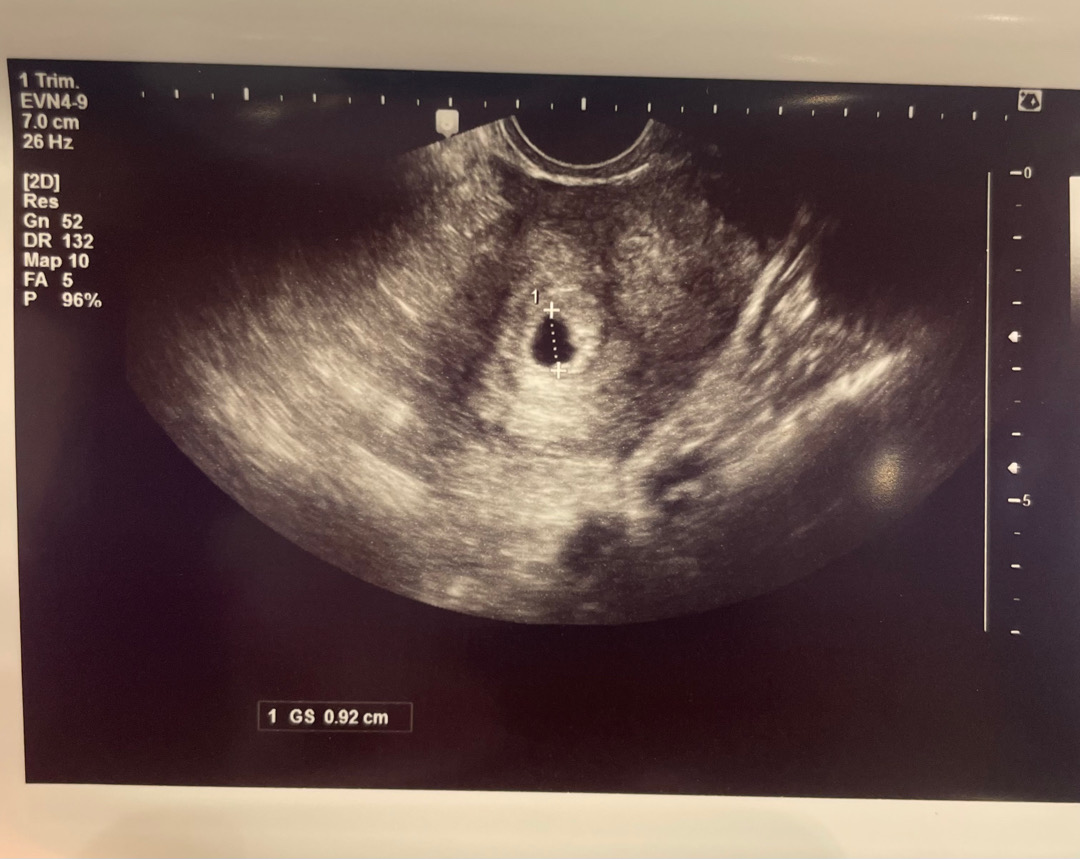

막생 1월3일이고 오늘 어플 상으로 5주라고 떠서 병원에 다녀왔어요. 애기집을 보긴 했는데 난황은 아직 안 보인다고 하네요 ㅠㅠ 집에 와서 초음파 사진 다시 확인하면서 발견한건데 애기집이 동그랗지가 않네요 ㅠㅠ 다른 분들 초음파 사진 보면 다들 애기집이 동그랗게 나오던데 혹시 정상 일까요? 너무 걱정이 돼네요 ㅠㅠ